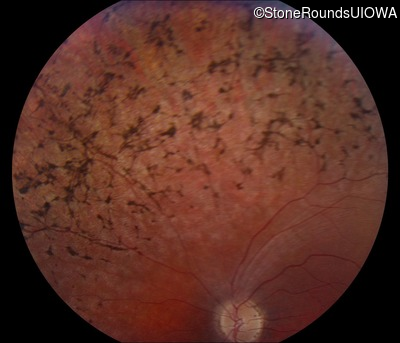

Fundus Photography - Right - 20/70 -2

Exemplar